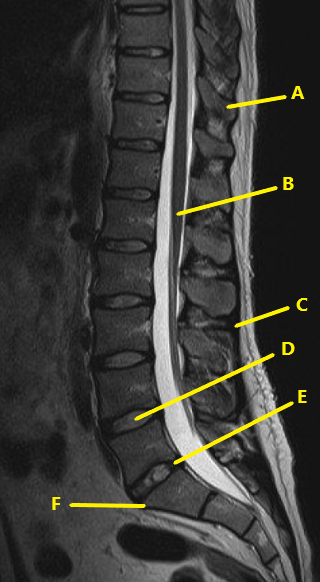

What letter is the intervertebral disc at L2-3 ?

C

What is letter D ?

nucleus pulposis

What is letter E ?

annulus fibrosis

What is D ?

supraspinatus tendon